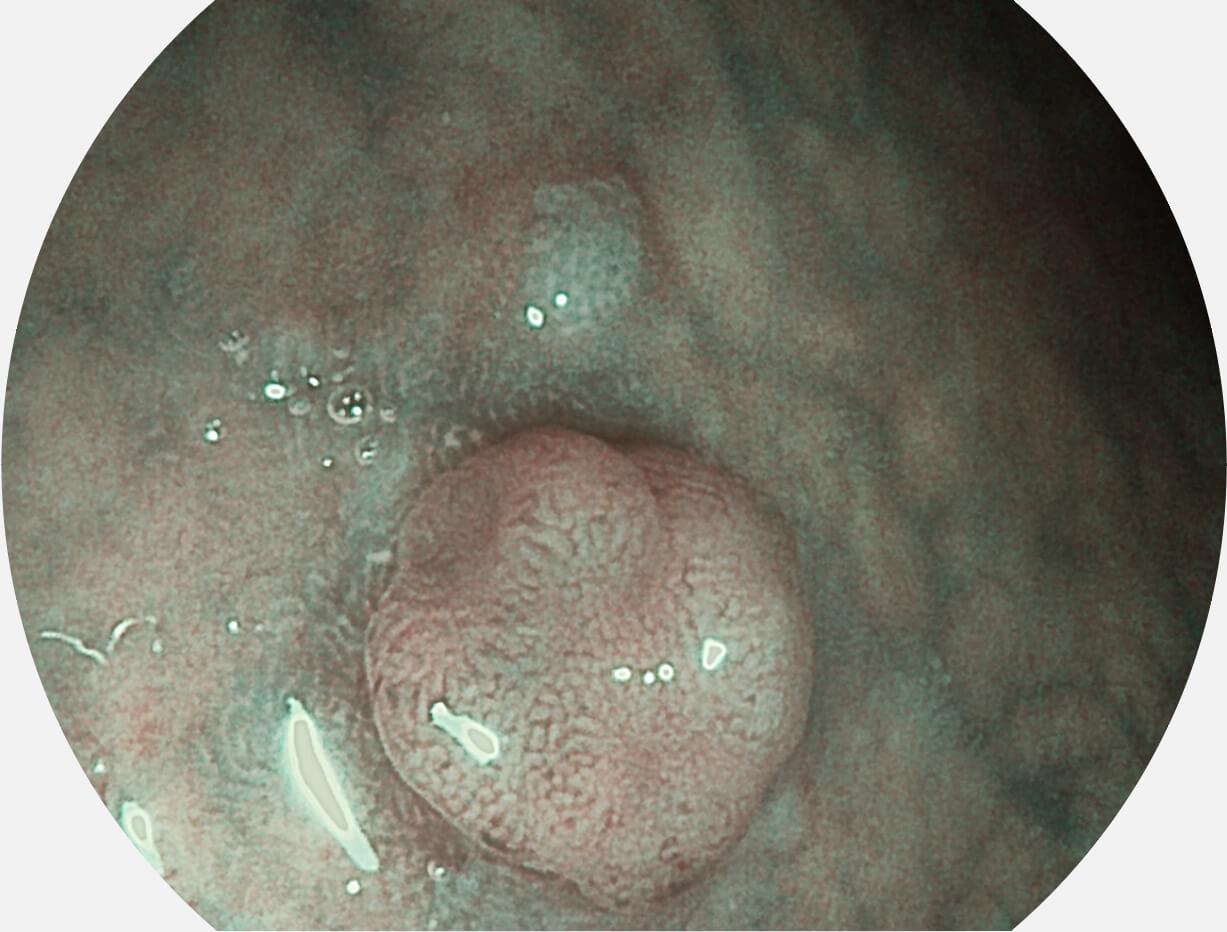

• 白光图像 SFI图像